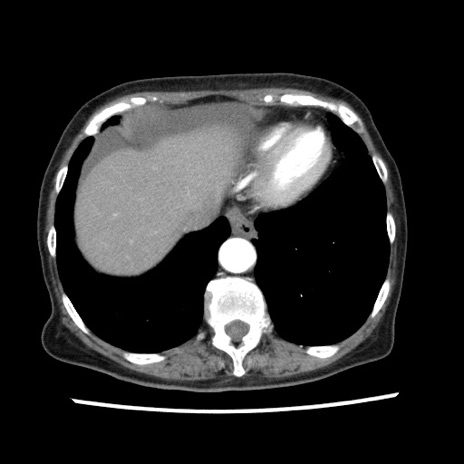

症例

【症例】80歳代女性

【主訴】腹痛

【現病歴】8時間前から腹痛あり来院。

【既往歴】糖尿病、脂質異常症、子宮体癌にて子宮全摘術

【身体所見】意識清明・会話良好だが腹痛で苦悶様、全腹部にわたって反跳痛と圧痛あり

【データ】WBC 13600、CRP 0.14、LDH 224、CK 90